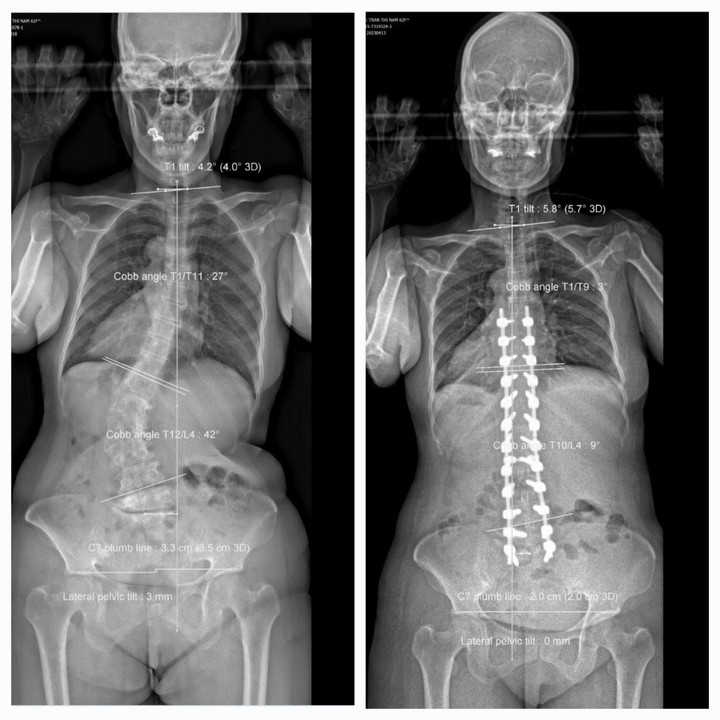

Kết quả chẩn đoán hình ảnh cho thấy bệnh nhân bị vẹo cột sống, còng cột sống ngực - lưng, mất ưỡn cột sống thắt lưng; biến dạng phức hợp khung chậu - cột sống, mất thăng bằng nặng toàn bộ cột sống, đường trọng lực đổ ra trước.

Sau khi chẩn đoán, ê-kíp đã phẫu thuật giải ép, ghép xương, cắt đĩa đệm hàn xương liên thân đốt cột sống thắt lưng kết hợp nắn chỉnh đường cong trước sau cột sống thắt lưng bằng ốc chân cung.

Sau phẫu thuật, bệnh nhân cao thêm 8cm, dáng người đi thẳng, người và phần đầu không còn đổ về trước khi đi hay đứng, hết đau tê hoàn toàn chân phải, chân trái còn tê rất ít, gần như bình thường, sức cơ hoàn toàn bình phục.

Ảnh chụp trước và sau phẫu thuật của bệnh nhân. (Ảnh: BVCC)